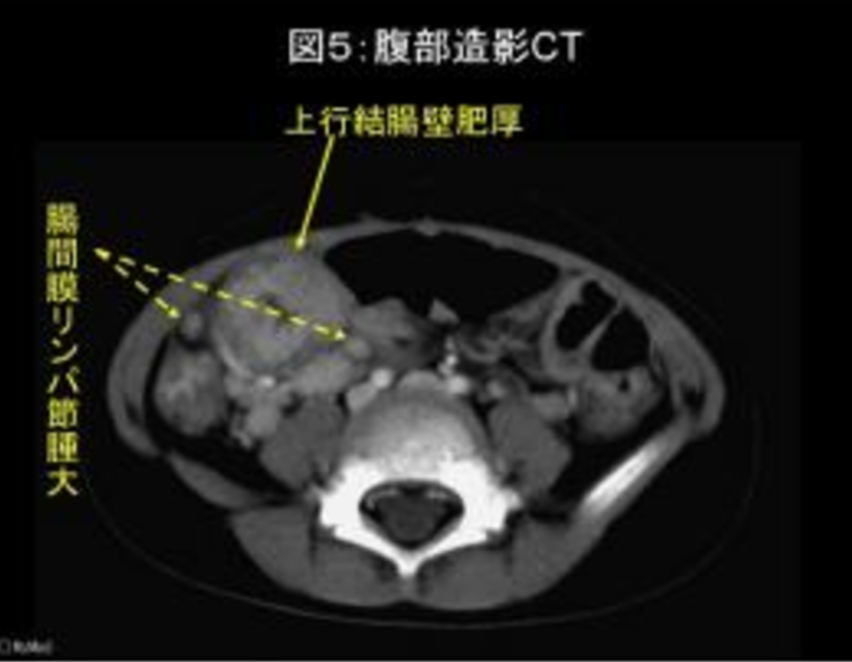

エルシニア腸炎はYersinia Enterobacteriaceaeによる腸管感染症であり、回腸末端に侵入し、有痛性の腸間膜リンパ節炎・右下腹部痛を生じさせる。

診断には便培養がキホンだが、常温下では他の菌の増殖に負けて検出されないことも。その他、CTが有用であり、回腸末端の炎症反応を認めるが、虫垂の腫大を認めなければエルシニア腸炎を考えることができる。

【エルシニア腸炎のCT画像紹介その1】